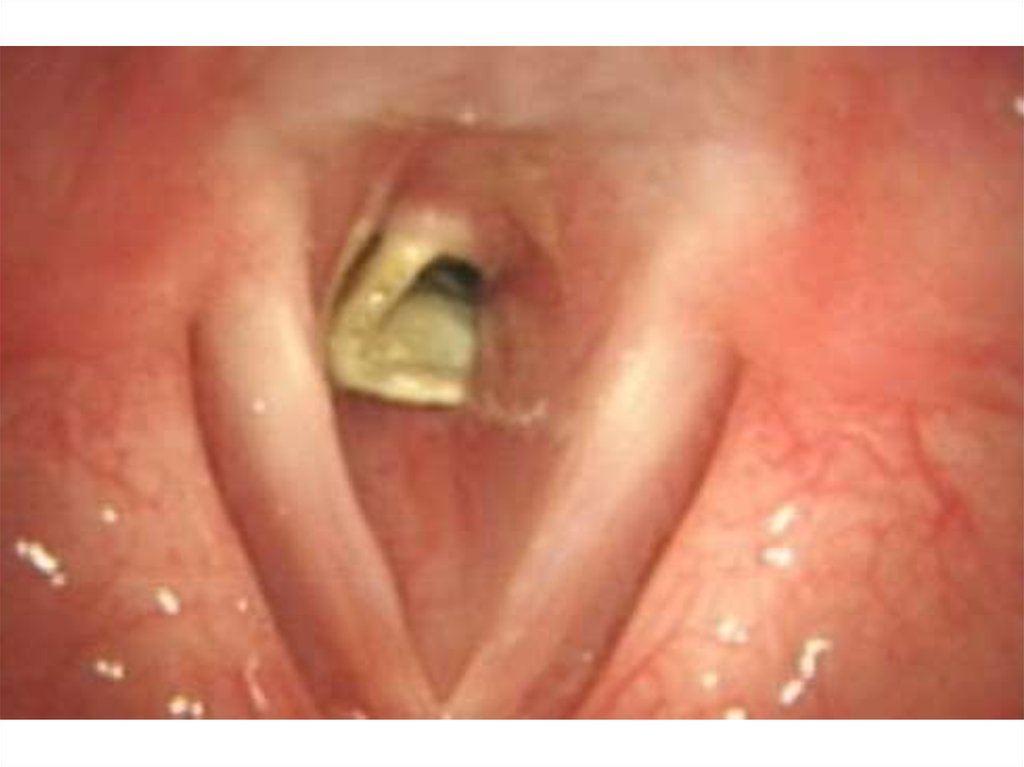

42. Инородные тела гортани и трахеи.

• Острое начало: кашель,

нарушения дыхания,

инспираторная одышка, цианоз,

осиплость голоса при

локализации в гортани, тупая

боль за грудиной – при

локализации в трахее.

49. Лечение:

• удаление при прямой

ларингоскопии или

трахеобронхоскопии, при

необходимости – трахеотомия,

• Прием Геймлиха,

• Коникотомия.